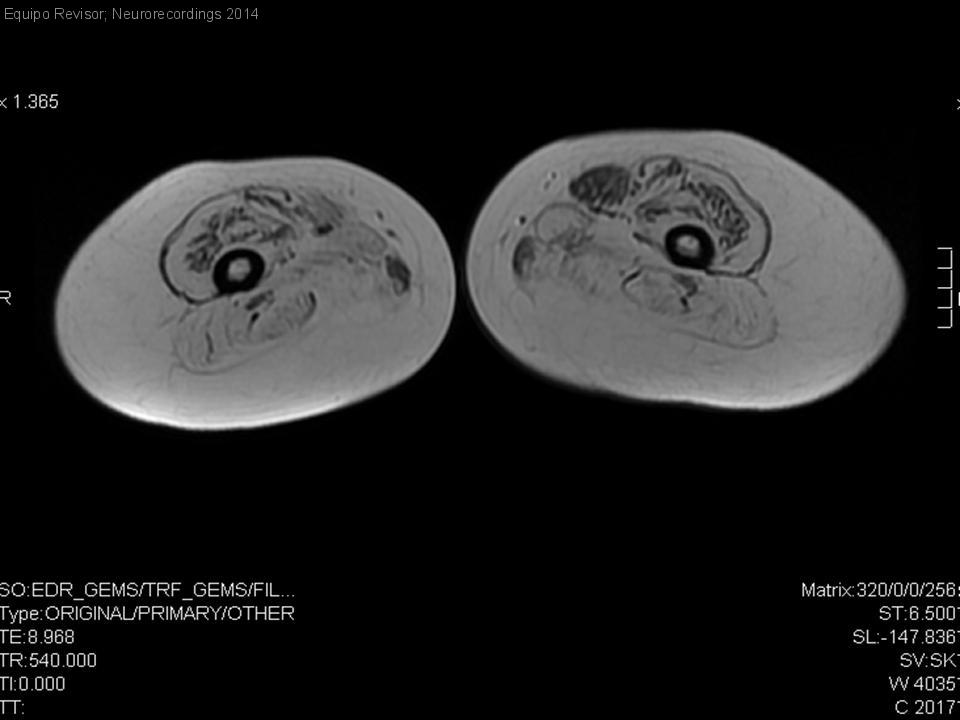

Distrofia de cinturas tipo 2A - Calpainopatía

Diagnóstico final: Distrofia de cinturas tipo 2A - LGMD2A

Neurología: Neuromuscular / ataxias

Etiología: Genético / idiopático